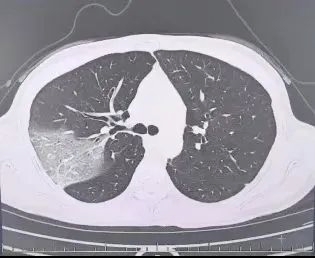

肺炎图片来源于稿源单位

结果情况反而进一步加重:好几叶肺都出现了“白肺”现象,指间血氧饱和度只有88%,血心肌酶谱、肌钙蛋白的指标、肝功能的指标也出现了明显的异常。

肺炎图片来源于稿源单位

所以,肺炎也是流感最常见的并发症之一,可引发包括原发流感病毒性肺炎、继发细菌性肺炎、细菌和病毒混合感染性肺炎,会有高热、咳嗽、咳痰、呼吸困难等症状,严重时可出现呼吸衰竭。